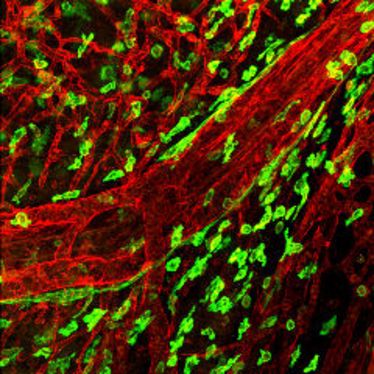

1. Small Animal Imaging Workshop in Münster

1. Small Animal Imaging Workshop in Münster

22.11.2010

- 26.11.2010

1. Small Animal Imaging Workshop in Münster

1. Small Animal Imaging Workshop in Münster

22.11.2010

- 26.11.2010

1. Small Animal Imaging Workshop in Münster

1. Small Animal Imaging Workshop in Münster